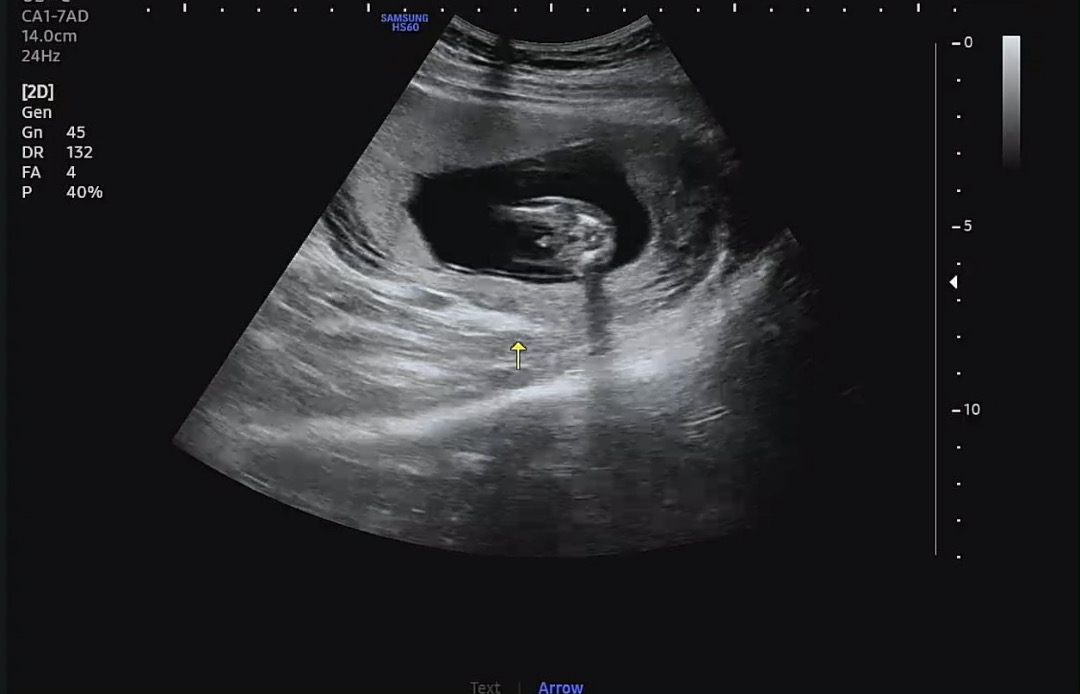

14주차 성별 확인해주세요

아들일까요…?

어우 존재감이 확실하네요..!

아들같아요!